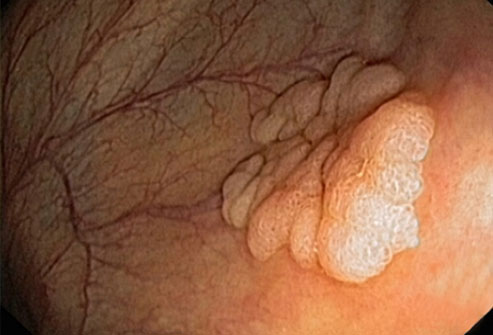

结直肠癌

大多数结肠癌是大肠内壁生长的息肉发展而来的。息肉可能是也可能不是癌细胞。如果息肉属于癌细胞,那么癌细胞可能会扩散到身体的其他部位。在息肉癌变前就将其移除,能够完全预防结肠癌。

结直肠癌筛查

结肠镜检查是一种常见的结直肠癌的筛检方法。医生会使用结肠镜进行检查。如果发现息肉,医生可能在检查过程中将其移除。另一种测试是更灵活的乙状结肠镜检查,这种检查只会检查结肠下部。如果你的风险水平属于平均状态,筛查通常从50岁开始进行。